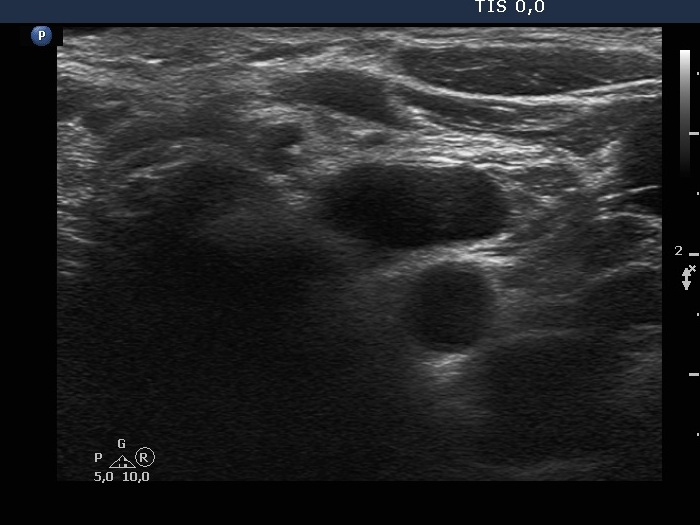

Parathyroid lesions - case 97 (ultrasonographic picture 11)

Right lobe, longitudinal scan